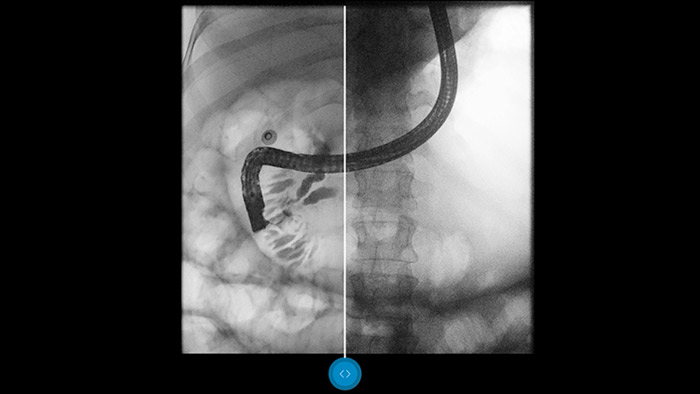

Vergleichen Sie Dynamic UNIQUE mit einer klassischen Bildverarbeitung und lassen Sie sich überzeugen.

Dynamic UNIQUE zeichnet sich durch eine intelligente, raumzeitliche Rauschunterdrückung, temporale Helligkeitsstabilisierung sowie Echtzeit-Multiskalen-Bildoptimierung aus, um eine qualitativ hochwertige Bildverarbeitung in Echtzeit zu ermöglichen.